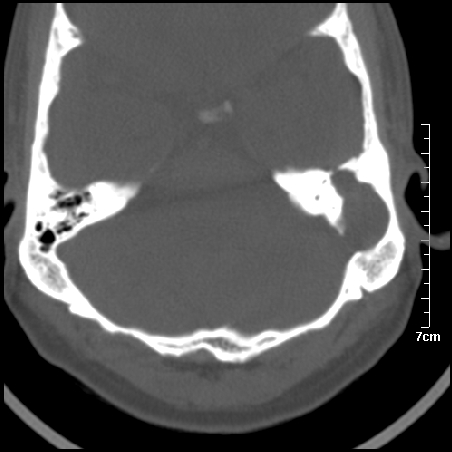

病例2

m/27